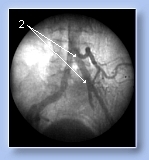

Суть операции заключается в том, что под рентгенотелевизионным контролем, чрезкожно, не рассекая тканей, тонкий оптоволоконный лазерный световод(1) подводится к месту сужения(2) или закупорки сосуда и с помощью лазерного излучения(3) производится разрушение атеросклеротических тканей(4) на мельчайшие частицы и восстановление проходимости и просвета сосуда(5).

До операции

1. окклюзия

общей

подвздошной

артерии слева

|

После операции 2.восстановление проходимости общей подвздошной артерии слева |